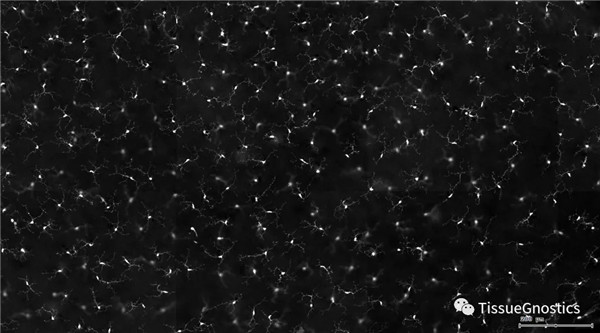

單通道灰階圖(↑:FITC,↓:Texa Red)

根據(jù)染色強度,染色面積,細胞形態(tài)學,利用正反向回溯功能和設(shè)門圈選Gating,排除雜質(zhì),細胞碎片,黏連細胞(綠色框線標記),獲得神經(jīng)元胞體,(粉色框線標記),并將胞體按照面積分為兩類(散點圖)。

由于該視網(wǎng)膜樣本是標記的小膠質(zhì)細胞,根據(jù)面積將神經(jīng)胞體分為兩類(Small bodycell,Big bodycell),反向回溯Big bodycell中的細胞后,應用Input Gate功能篩選短粗的神經(jīng)纖維,作為激活態(tài)的小膠質(zhì)細胞。